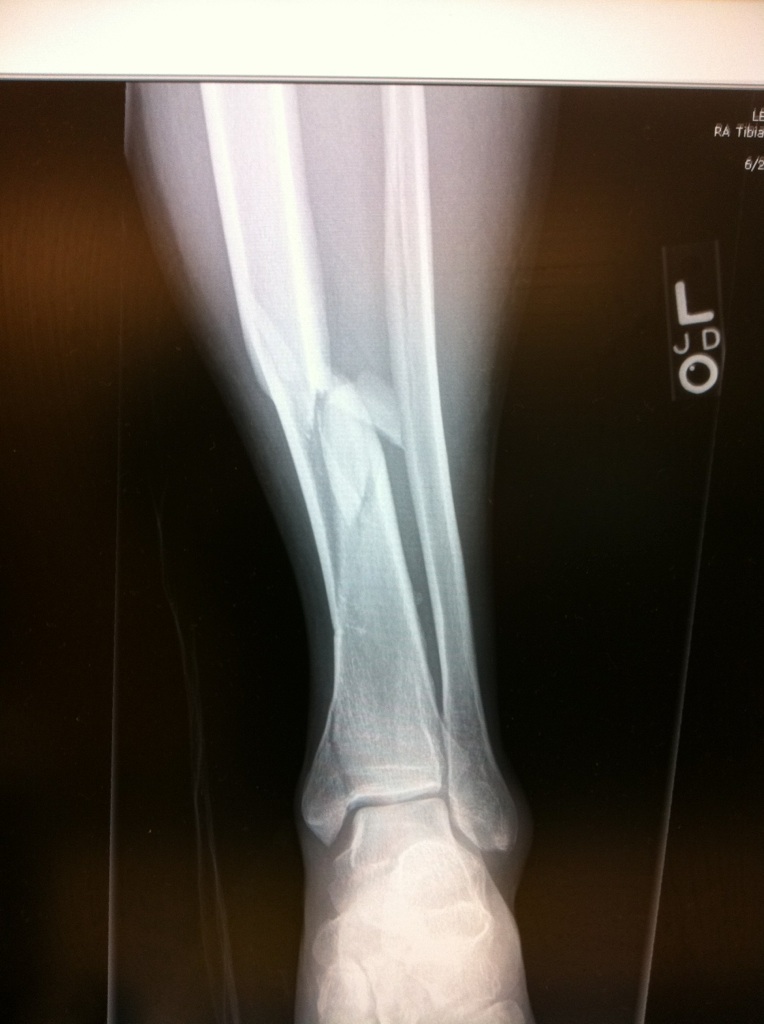

Meanwhile back at Gresham medical center I still have not seen my x-rays. Fortunately a nurse understood my concerns and snapped a couple of pictures of the computer screen on her iPhone and sent them to me. The shot at the top of this blog is one of those pictures. I take one look and know I am in trouble, this is no normal surgery if I want leg length and rotation to stay normal. I take the images and email them to Dr. David Paul Barei and call him, Yens Chapman introduced me to Dr. Barei. Because Dr. Barei knows me and knows I would not call if it was not urgent he steps out of rounds to take my call. One look at the x-rays and he says:

– well these are going to be complicated. Did they talk to you about the fracture in the ankle joint? No, well that is going to be tough and did they talk with you about the vascular damage? No, well it looks like you leg rotated more than 180 degrees when it was broken and I would estimate you have a 50% chance of keeping your lower leg. You need to get yourself transferred to Harborview now. I explain they refuse to transfer me and he says: “What do you mean they will not transfer you? Put the Dr on please. I hand my phone to the local Dr basically says a few yes’s and a few no’s in response to Dr. Barei’s questions and then says OK, hands me back the phone and says I am getting transferred to Harborview.